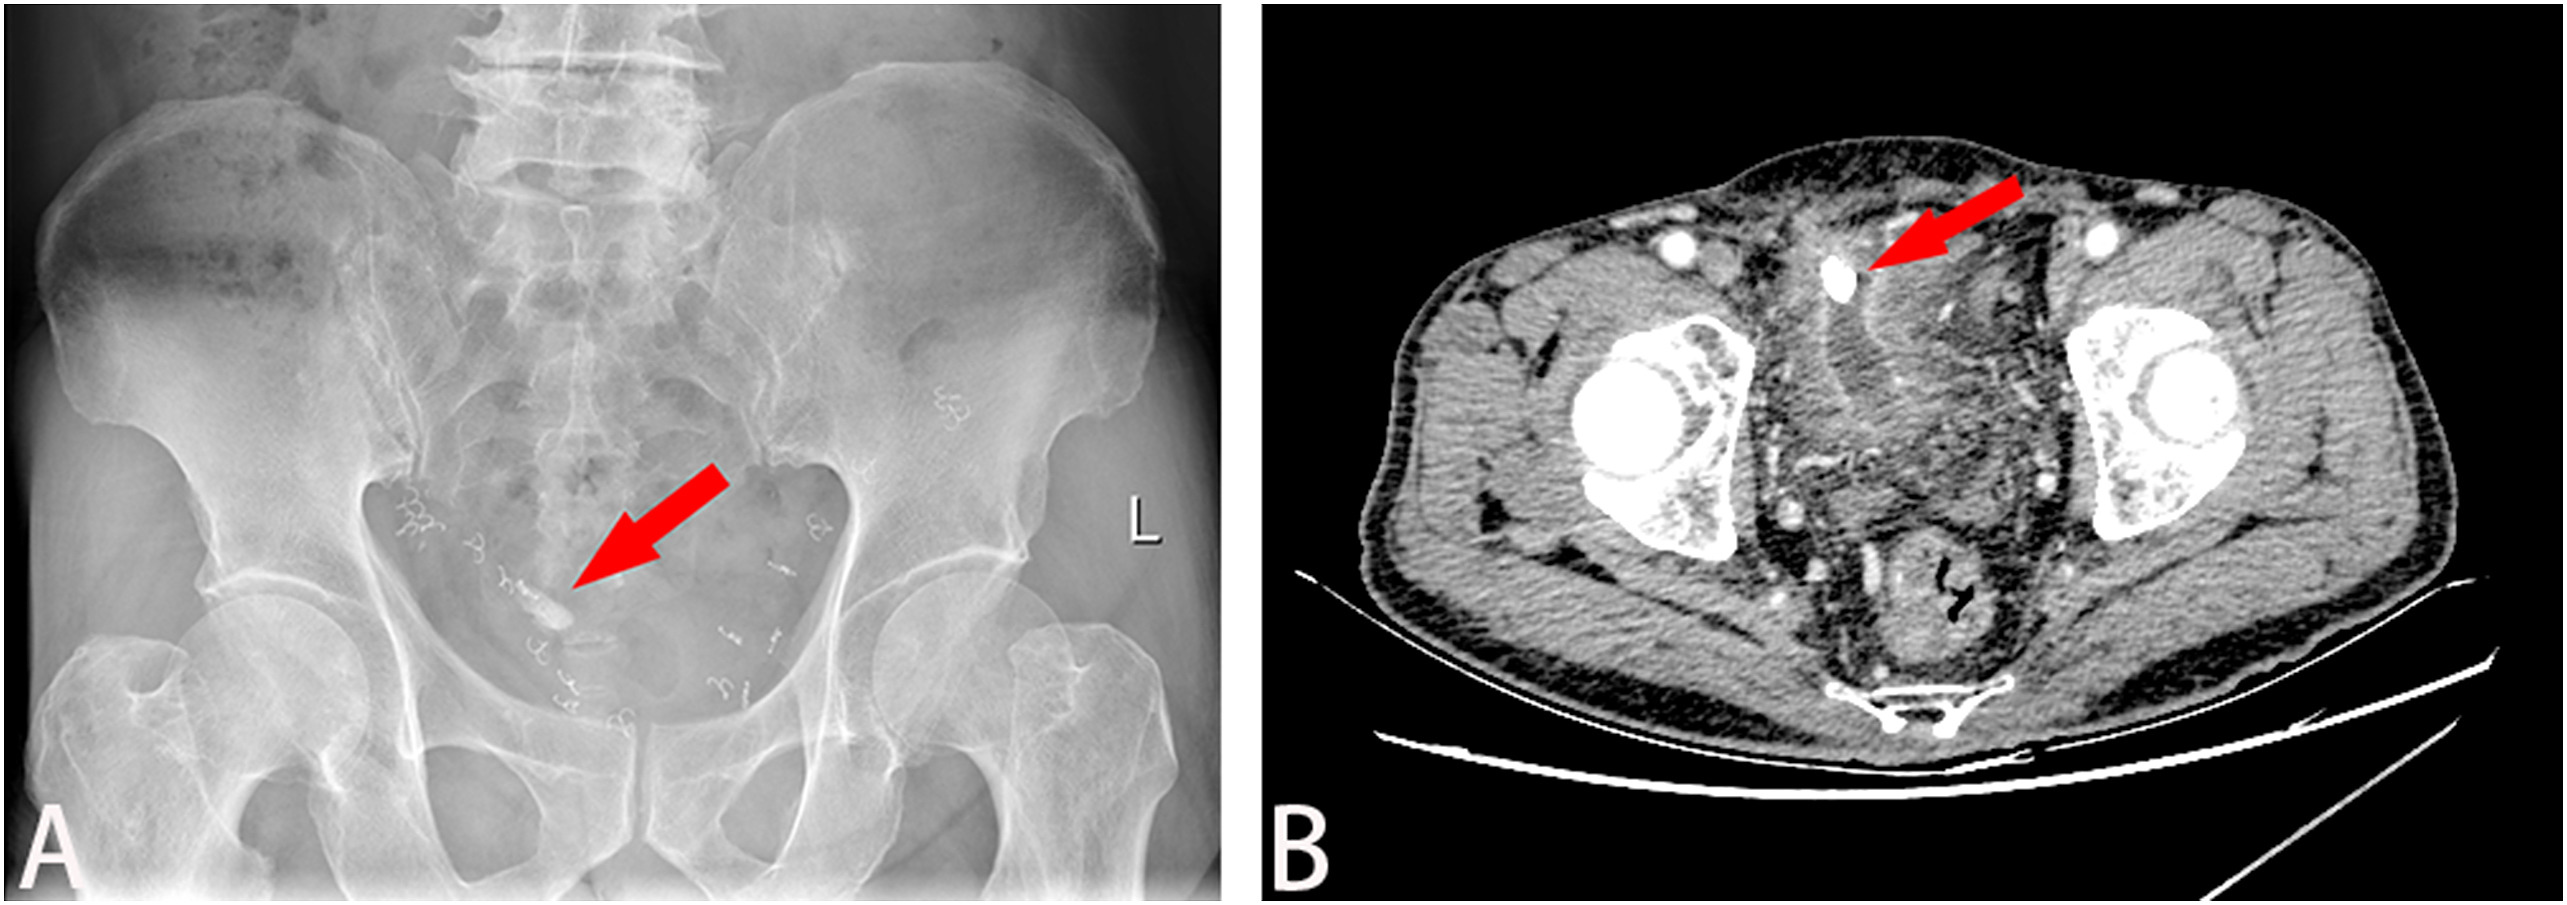

和超声检查均显示膀胱结石(图1A)。

图1 (A)腹部平片显示膀胱结石(红色箭头);(B)增强CT显示附着在膀胱前壁的结石(红色箭头)

从上面两张影像图中,大家有没有观察到些许端倪呢?眼尖的朋友一定注意到骨盆区域的异常影像,这到底是什么呢?

最初医生认为是膀胱憩室结石。进一步行增强CT检查

显示,膀胱前壁上附着一大小约17×14×10mm的结石,骨盆内有多个金属钉,怀疑是用于固定补片的手术钉(图1B)。三维重建CT(3D-CT重建)显示补片侵蚀膀胱,结石与网片粘连紧密(图2)。膀胱镜